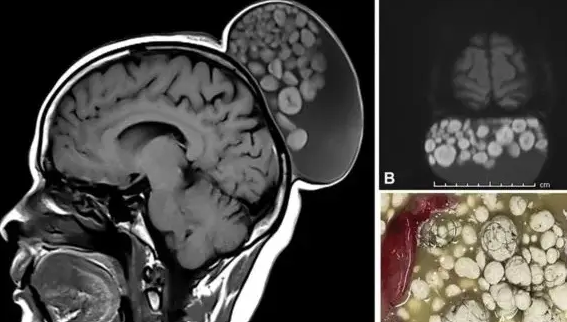

Uma indiana de 51 anos retirou um cisto da cabeça, semelhante ao formato de um saco de bolinhas de gude. O caso foi registrado em maio deste ano, mas divulgado apenas agora pelo periódico médico Radiology.

Exame médico revela semelhança de caroço, a um saco de bolinhas de gude. – Foto: Divulgação/RadiologyExame médico revela semelhança de caroço, a um saco de bolinhas de gude. – Foto: Divulgação/Radiology

A ressonância magnética apontou frios de cabelos aglomerados de gordura no cisto da paciente, o que aparentou bolinhas de gude, conforme publicado pelo portal Itatiaia.

Após a retirada do caroço, os médicos descobriram que os aglomerados de gordura, na verdade eram compostos de queratina, proteína utilizada para forma cabelos e unhas na cama externa da pele.